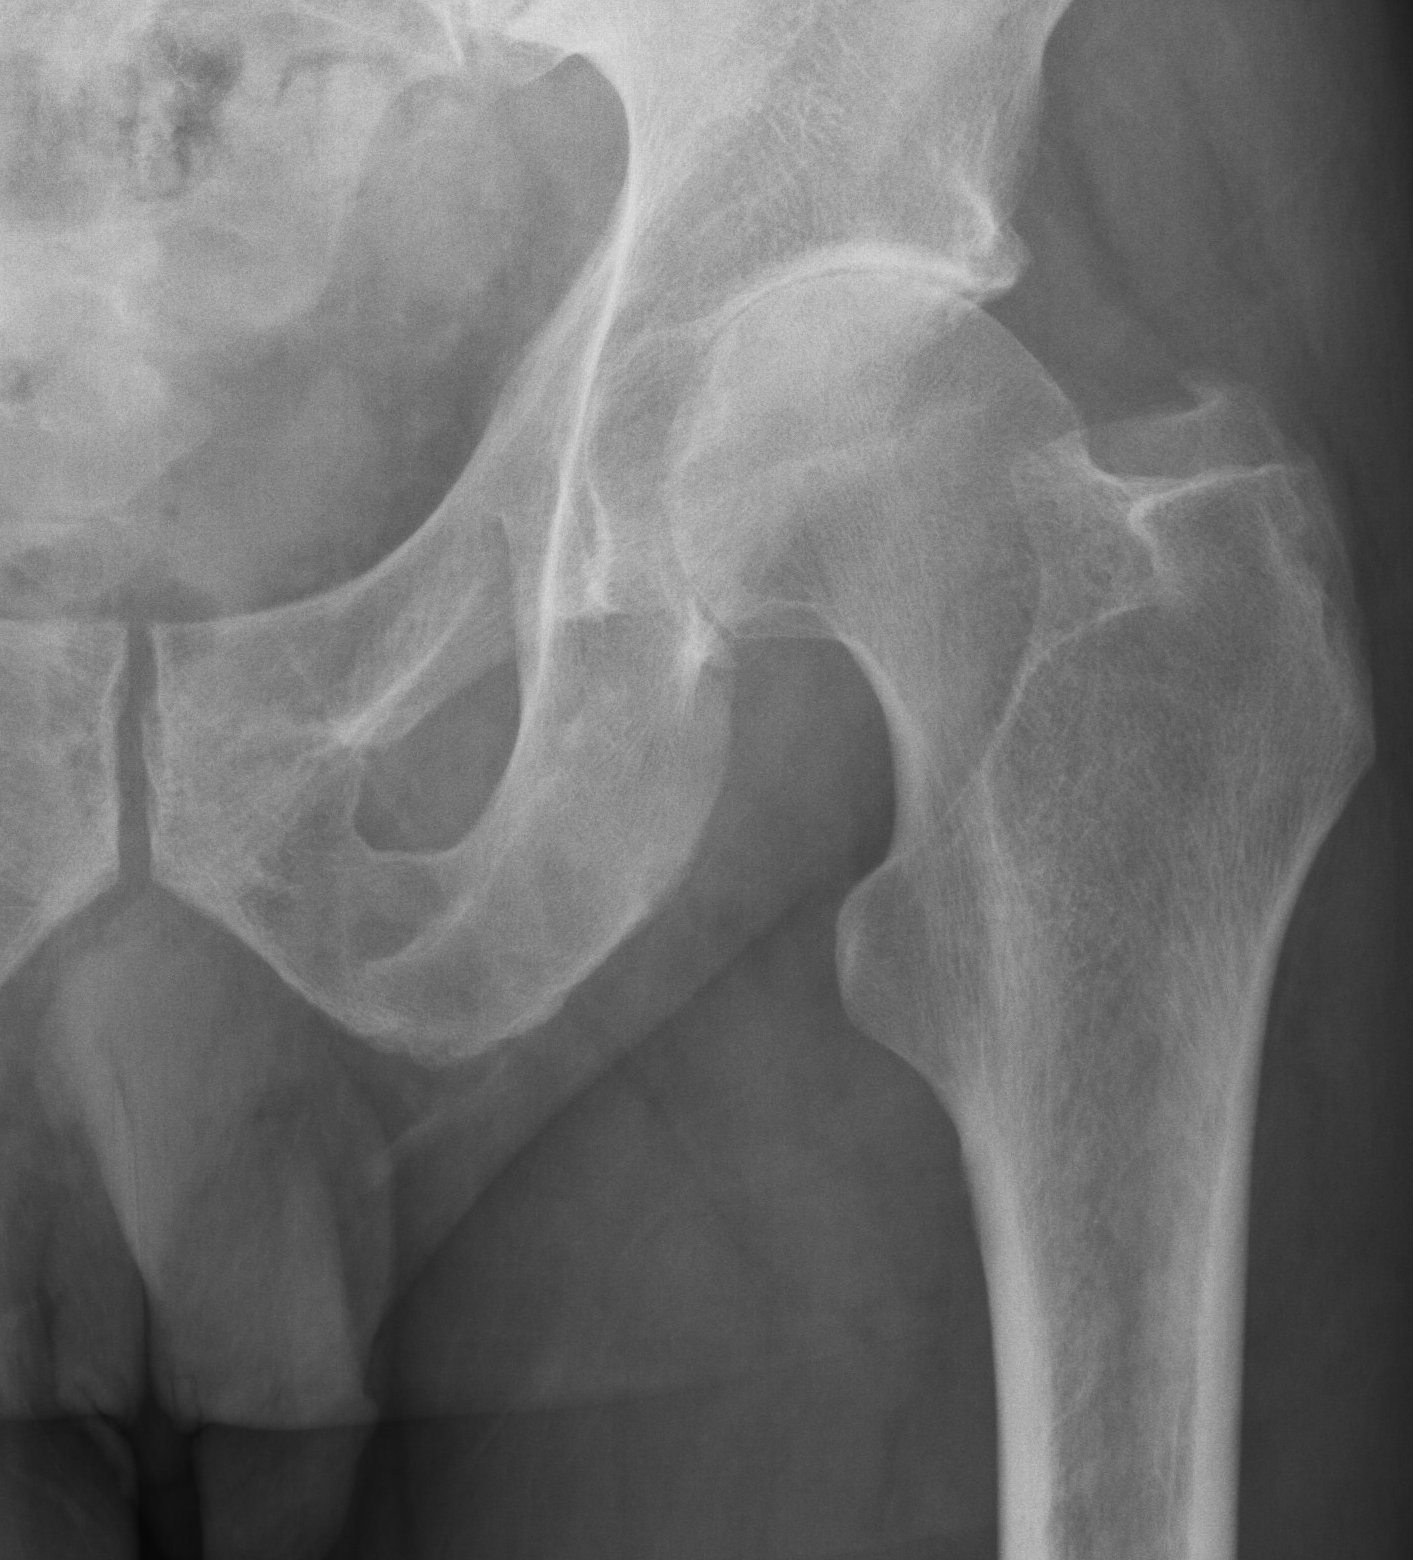

Patients usually present with a very rapid onset of severe pain and signs of toxicity. In patients who are very immuno-compromised there may not be the usual signs of systemic reaction to infection. In the early stages x-rays may mimic arthritis or AVN.

MRI is very sensitive but may still struggle to differentiate between advanced sepsis and AVN.